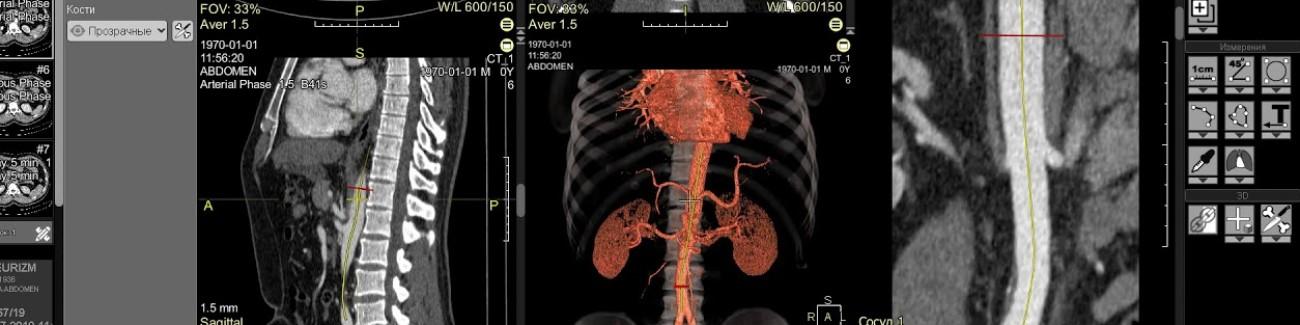

ALM DICOM Viewer delivers top-tier support and services to hospitals, clinics, and radiology centers for efficient imaging operations.